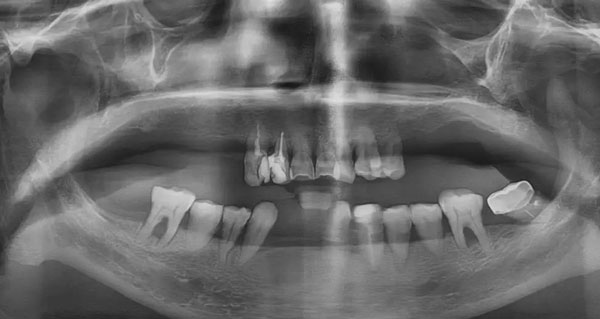

鄧女士種牙前全景片

多顆牙缺失+牙周病

讓她嘴角干癟,前牙外凸,嚴重影響面型